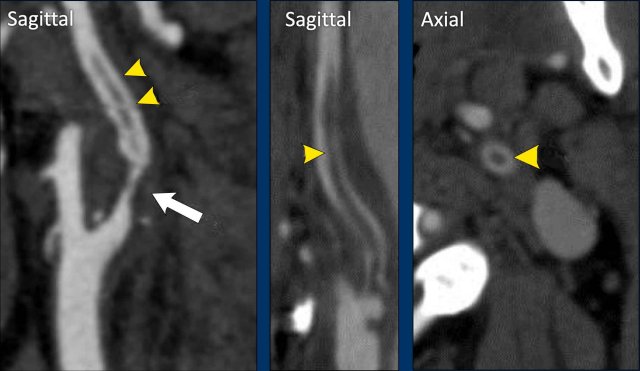

Carotid Web

A carotid web is a shelf-like lesion along the posterior wall of the internal carotid artery bulb and an under-recognized cause of stroke in young individuals.

Several studies suggest that patients with a carotid web have a high risk of recurrent stroke.

On the saggital view of the CTA the shelf-like protusion on the dorsal wall of the ICA bulbus is seen.

This is the typical configuration location for a carotid web.

However, for the definite diagnosis of a carotid web a ridge connecting the lateral and medial wall of the internal carotid artery must be seen in the axial view (arrow right image).

Carotid webs can differ in size.

In this case the

carotid web is much smaller than in te previous example.

However, the imaging

criteria for the diagnosis of a carotid web still apply.

On the sagittal images

a self-like protrusion is seen on the dorsal aspect of the internal carotid

artery (arrow left image).

On the axial images the ridge of the carotid web

is seen connecting the lateral and medial wall of the internal carotid artery (arrow).

If you only look at the axial images,

you may miss a web.

The red arrow points at the ICA and

ECA, but no web is seen..

Only with by angulating the axial

plane perpendicular to the longitudinal axis of the ICA (green line and green

arrow) you will notice the web (ridge

connecting the lateral and medial wall of the ICA.

Of course the sagittal

reconstructions are superior for detecting a web.